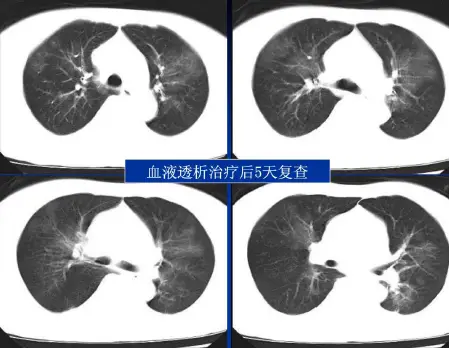

病例:男,33岁,急性肾衰肺水肿。CT表现:①肺间质性肺水肿:两肺血管束增多、增粗,边缘模糊;②肺泡性肺水肿:两肺透光度减低,并见广泛性分布结节样、斑片样密度增高影及毛玻璃样影,边缘模糊,以两肺内、中带分布较明显,形成典型“蝶翼征”;③胸腔积液。